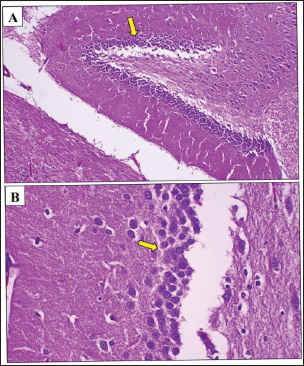

Histological examination revealed significant differences between the experimental groups. In the negative control group, the hippocampal neurons appeared normal morphology with intact, with a well-preserved dentate gyrus and no detectable amyloid beta protein aggregates, indicating a healthy brain tissue (Fig. 1).

Fig. 8. Photomicrograph of the hippocampus of a control-positive rat. (A, B) Neurodegeneration (black arrow) was observed in stratum granulosum cells of dentate gyrus area of the affected hippocampus, where cytoplasmic vacuoles were observed within granule cells. However. The density of the granule cells (yellow arrow) was less compared with the control negative group due to neuron loss in the dentate gyrus area. Also, there was a significant loss in neurocyte number of the Cornu Ammonis (CA) regions 2 and 3 (blue arrow). H&E. A: 100x and B: 400x.